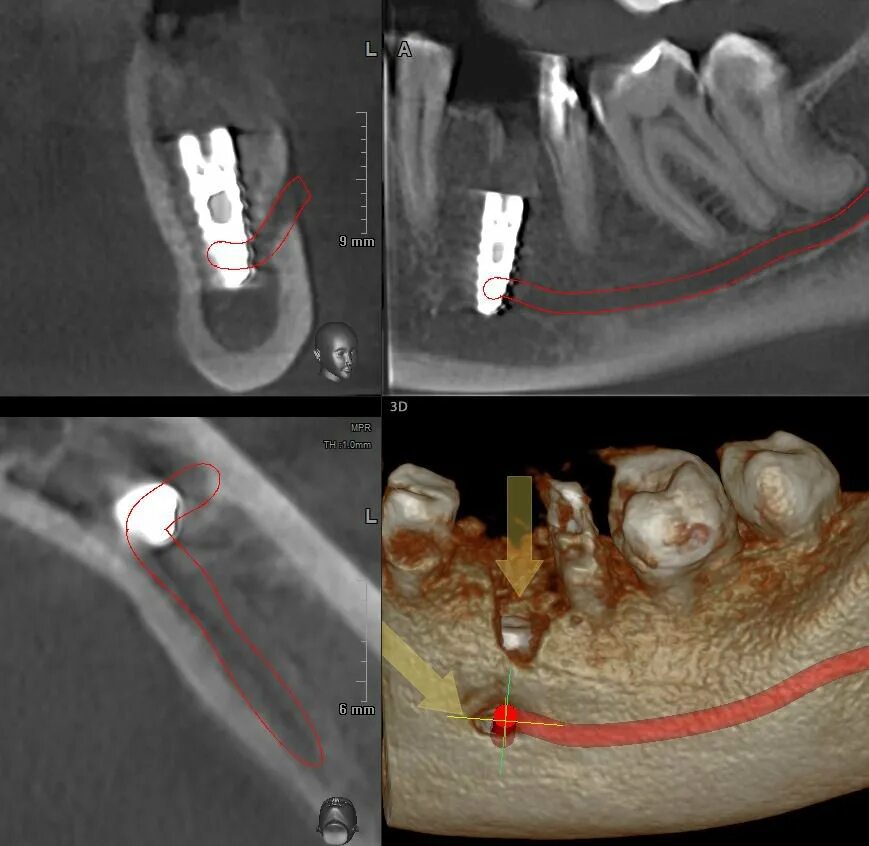

Picasso кт